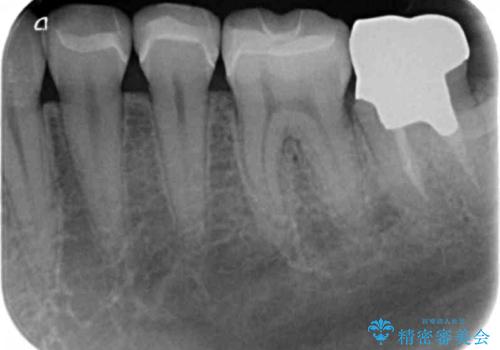

- 銀歯を装着してから時間が経っているので一度外して審美的な修復治療を受けたい、と希望され来院されました。

銀歯周囲の天然歯を削らないよう、拡大鏡下で丁寧に銀歯を除去したのちに審美性・精密性に優れるセラミックインレーを用いた修復治療を行っていきます。